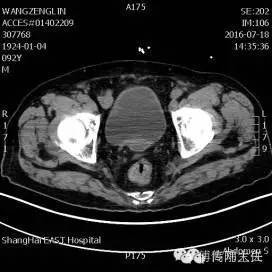

术前盆腔CT显示肿瘤位于直肠上段,伴有肠腔狭窄